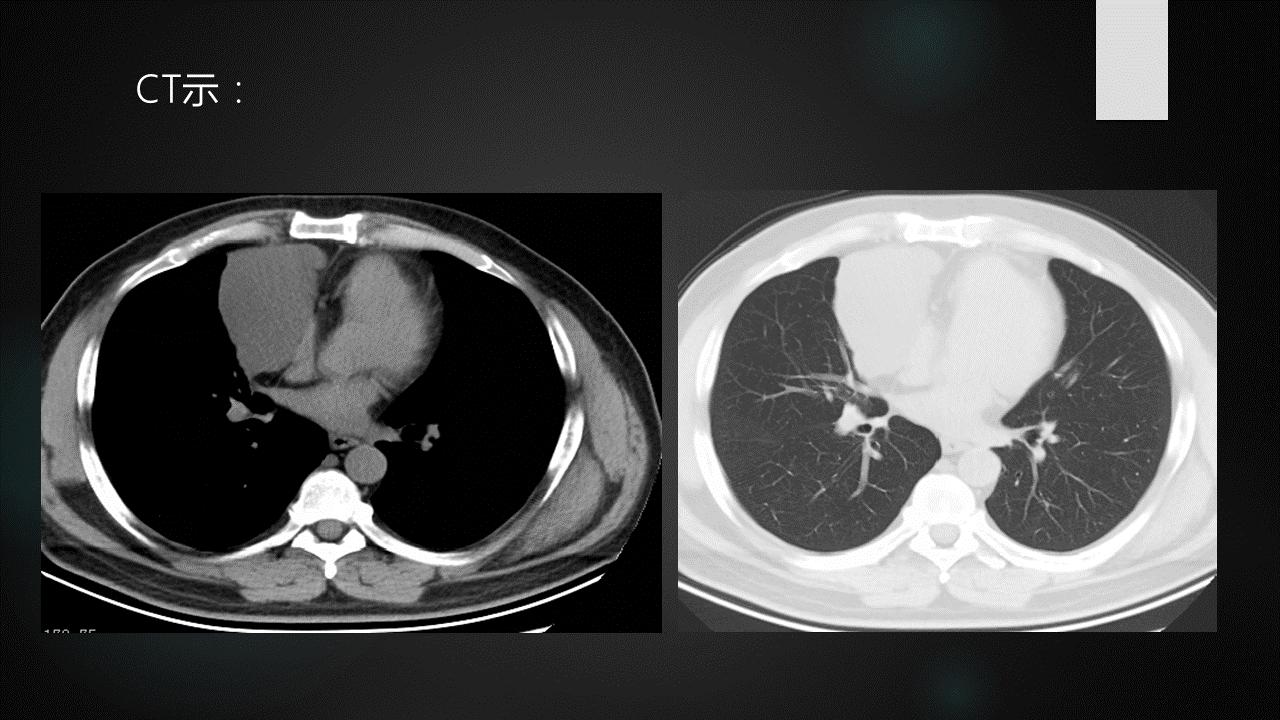

非侵袭性胸腺瘤CT图像

a. CT平扫示前上纵膈主动脉弓与胸骨间软组织密度肿块,密度均匀,边缘浅分叶状 b. CT增强示肿块均匀强化,肿块与主动脉弓之间脂肪间隙清晰